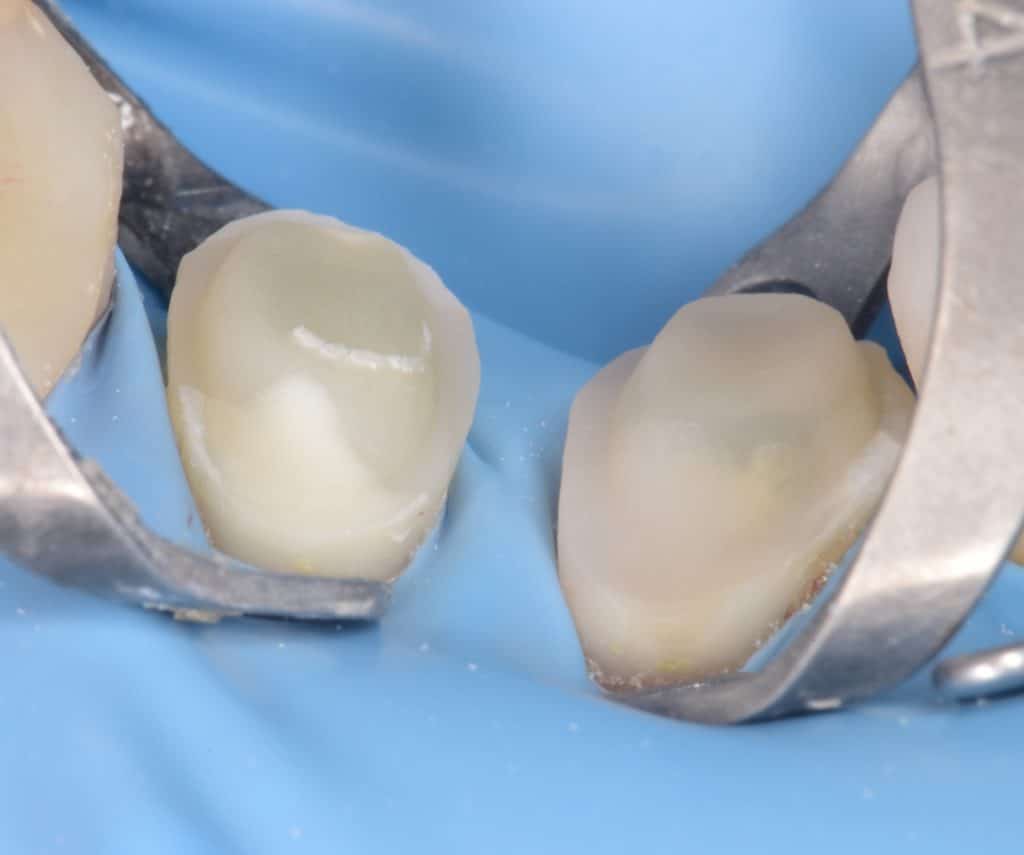

Preparation done , macro-core buildup for premolars

Cementation day, isolation with rubberdam, biobase air abraded

Buccal view showing the macro-core buildup